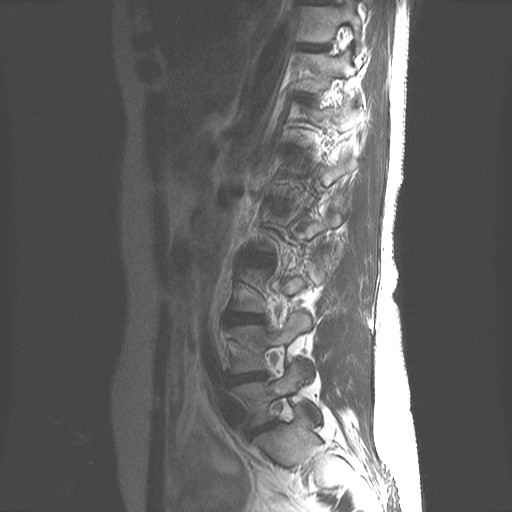

Lage Wervel Zuil